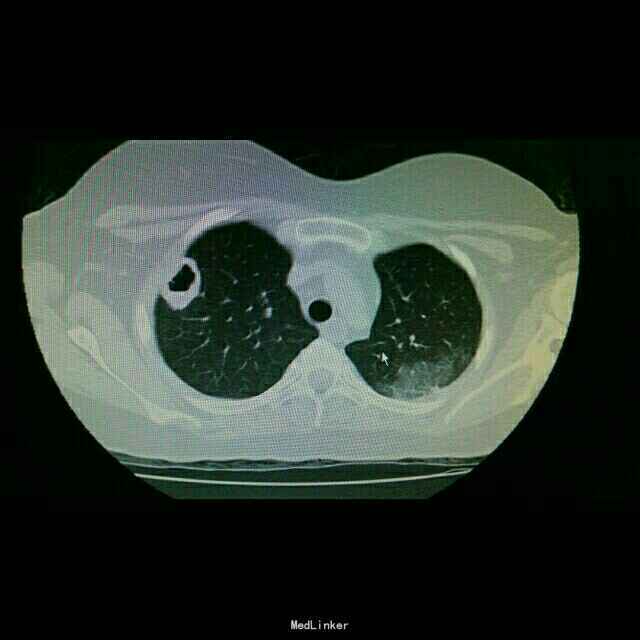

查体:双肺湿罗音,余无特殊。 辅查:9.10胸部CT双肺炎症。10.2原炎症部位出现空洞。10,21原炎症部位好转,空洞无明显变化。

诊断:肺曲霉病。 治疗:开始予以伏立康唑治疗,仍有发热,后予以两性霉素*B治疗。

随访:继续予以两性霉素B治疗,总量用至1g。 讨论:对于大剂量激素治疗,容易导致真菌感染。而所有抗真菌药物都是以两性霉素B为对照研究抗菌能力的。用要过程密切注意患者肝肾功能的情况。